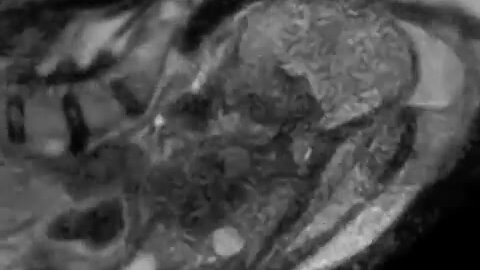

Роды через МРТ 📸